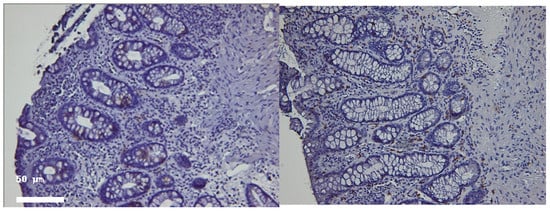

2.1. Histological Disease Activity

2.2. Distribution of T Lymphocyte Subsets

2.2.1. Cd4+ Lymphocytes

2.2.2. CD8+ Lymphocytes

4.7. Immunohistochemical Analysis